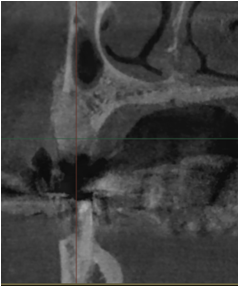

상악동이란 얇은 위턱뼈 위에 코와 광대 사이의 빈 공간을 지칭하는 해부학적 부위로,

상악동이 많이 확장되어 있는 경우 그만큼 임플란트를 심을 수 있는 잇몸뼈가 부족해져서 임플란트 식립이 어려워 질 수 있습니다.

상악동 골증강술은 상악동 내부에 조심스럽게 접근해서 뼈이식을 하여 임플란트 식립에 필요한 잇몸뼈를 만들어내는 난이도 높은 술식입니다.

얇은 상악동 막을 들어올려 뼈를 이식하는 상악동 골증강술은 시술 부위의 특성상 섬세한 기술이 필요합니다.

때문에 부작용의 우려가 존재하기에 풍부한 경험과 노하우, 안전한 장비를 갖춘 치과에서 치료를 받는 것이 중요합니다.